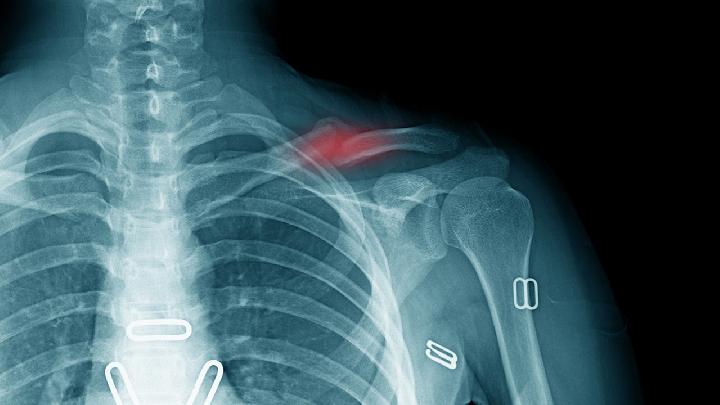

骨折的发生不仅是疼痛难忍,甚至还会对身体造成其他危害,所以在发生骨折以后一定要及时的就诊,积极的采取治疗措施,以免发生感染及其他严重后果,那么治疗骨折的医院该如何选择呢?